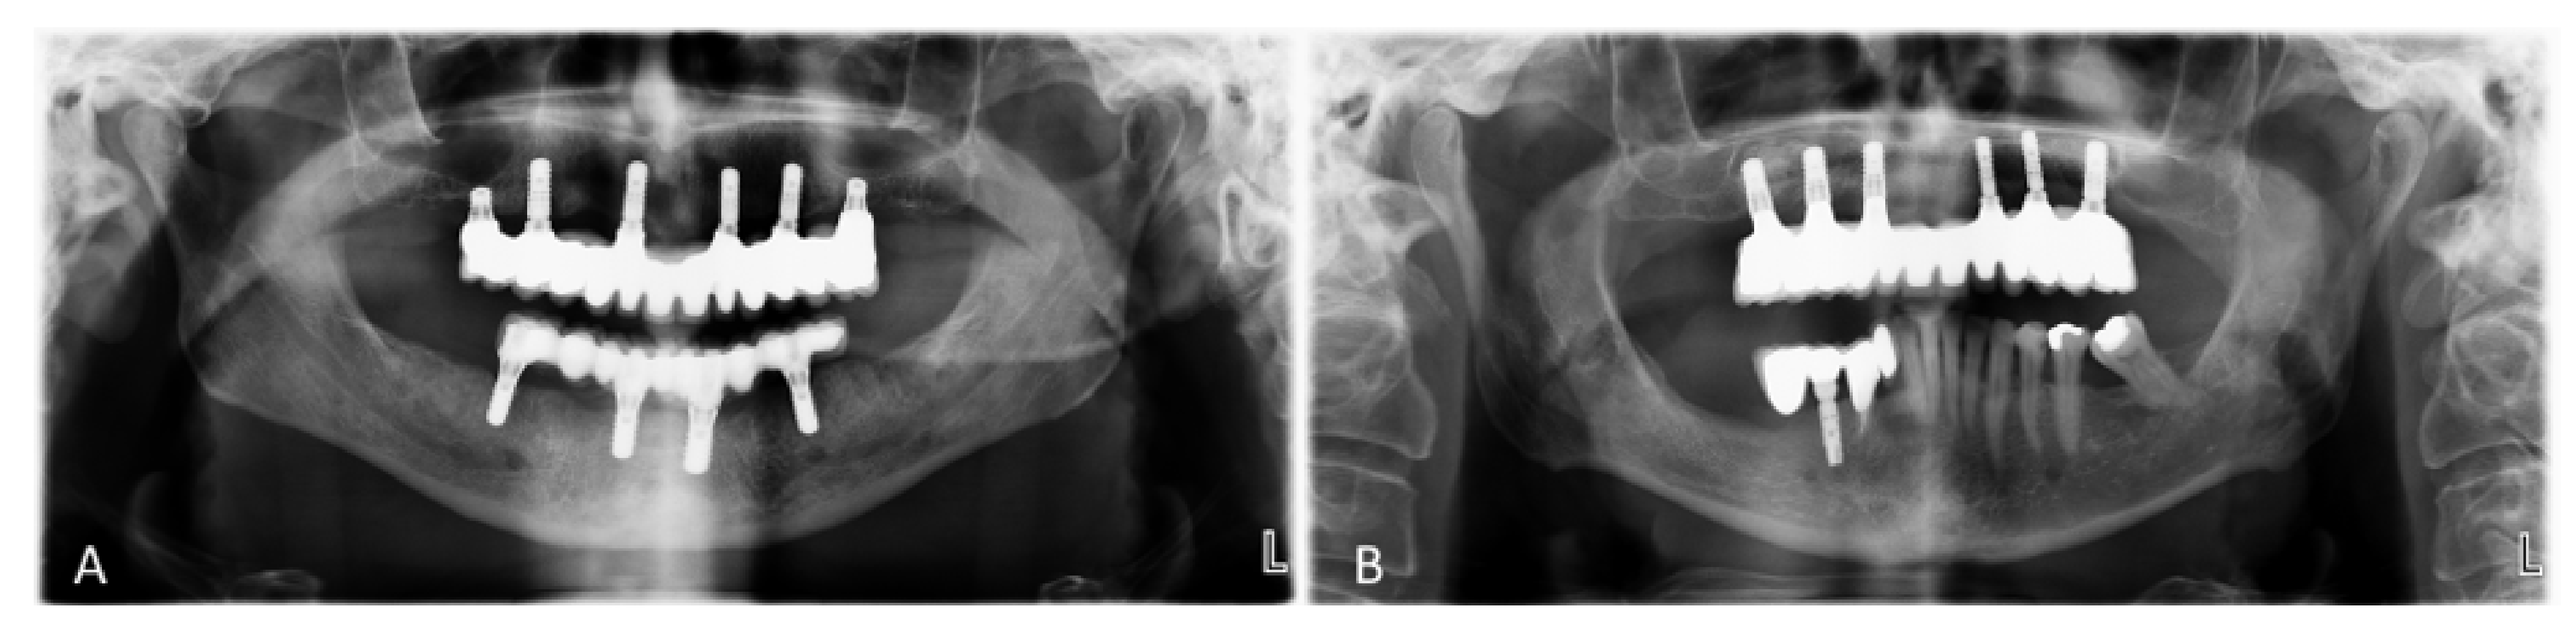

Two-Year Follow-Up of 4-mm-Long Implants Used as Distal Support of Full-Arch FDPs Compared to 10-mm Implants Installed after Sinus Floor Elevation. A Randomized Clinical Trial

2.6. Surgical Procedures in the Short Group (Test)

2.7. Surgical Procedures in the Standard Group (Control)